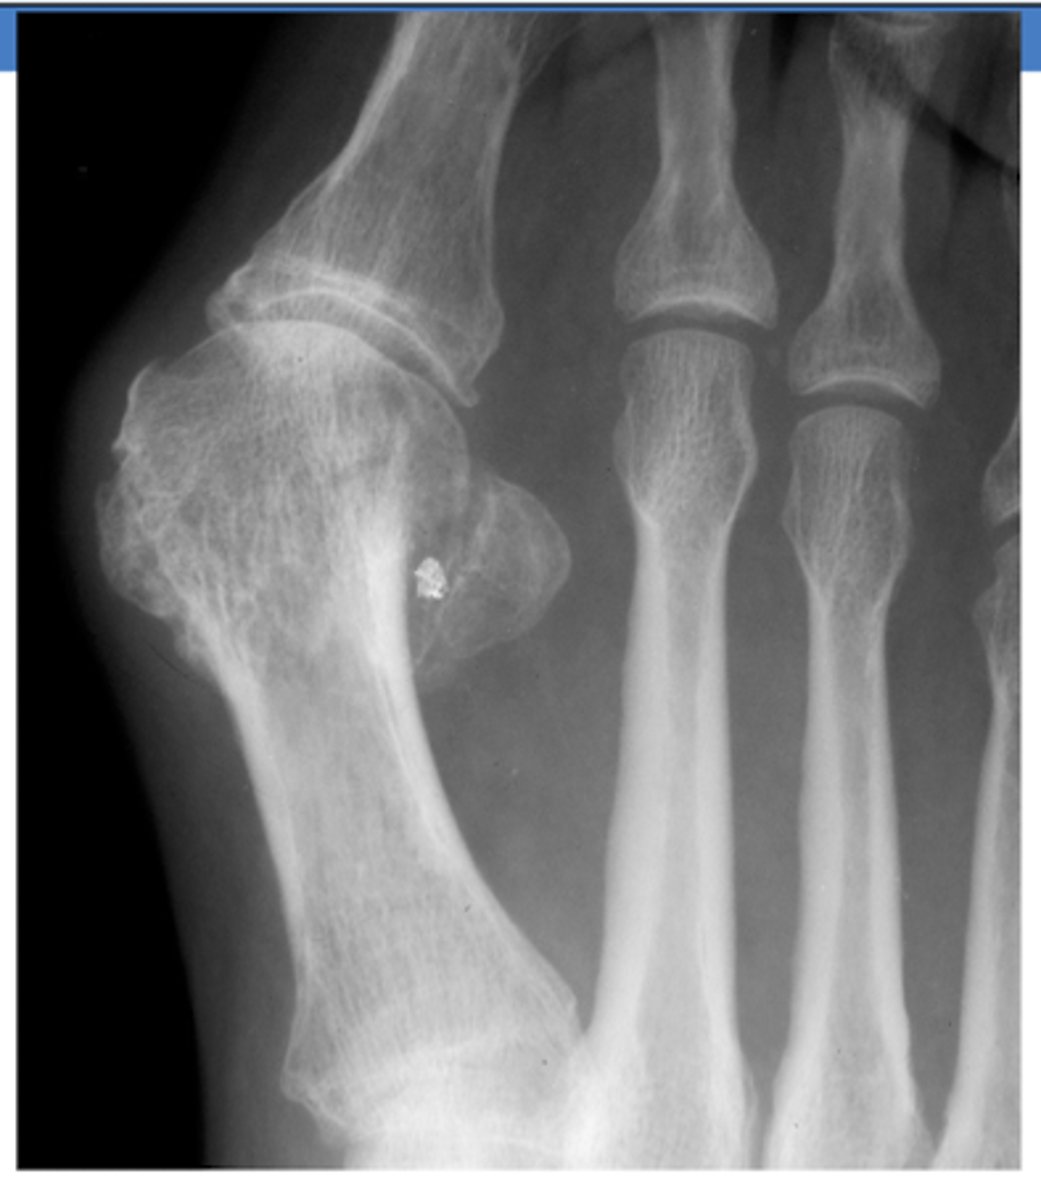

What term can be used to describe a lateral deviation of great toe?

hallux valgus (bunion)

What term can be used to describe a neurogenic arthropathy that affects the joints of the foot?

Charcot's disease

- leads to joint deformities and loss of sensory function in the affected limb

What can lead to the development of Charcot's disease?

uncontrolled DM

- with peripheral neuropathy

What TWO findings on XR are suggestive for Charcot's foot?

Decline in calcaneal inclination with equinus (inability to dorsiflex)

Rocker-bottom deformity

**will initially not appear on XR